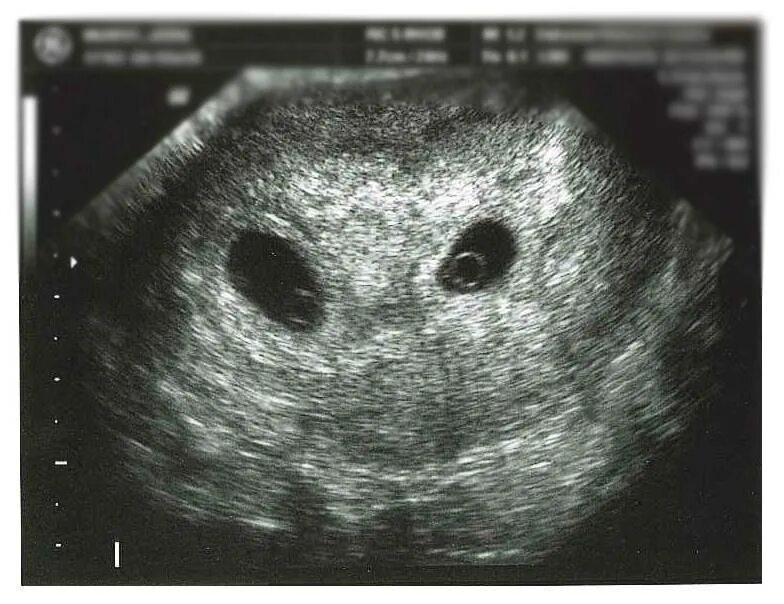

На каком сроке можно увидеть двойню